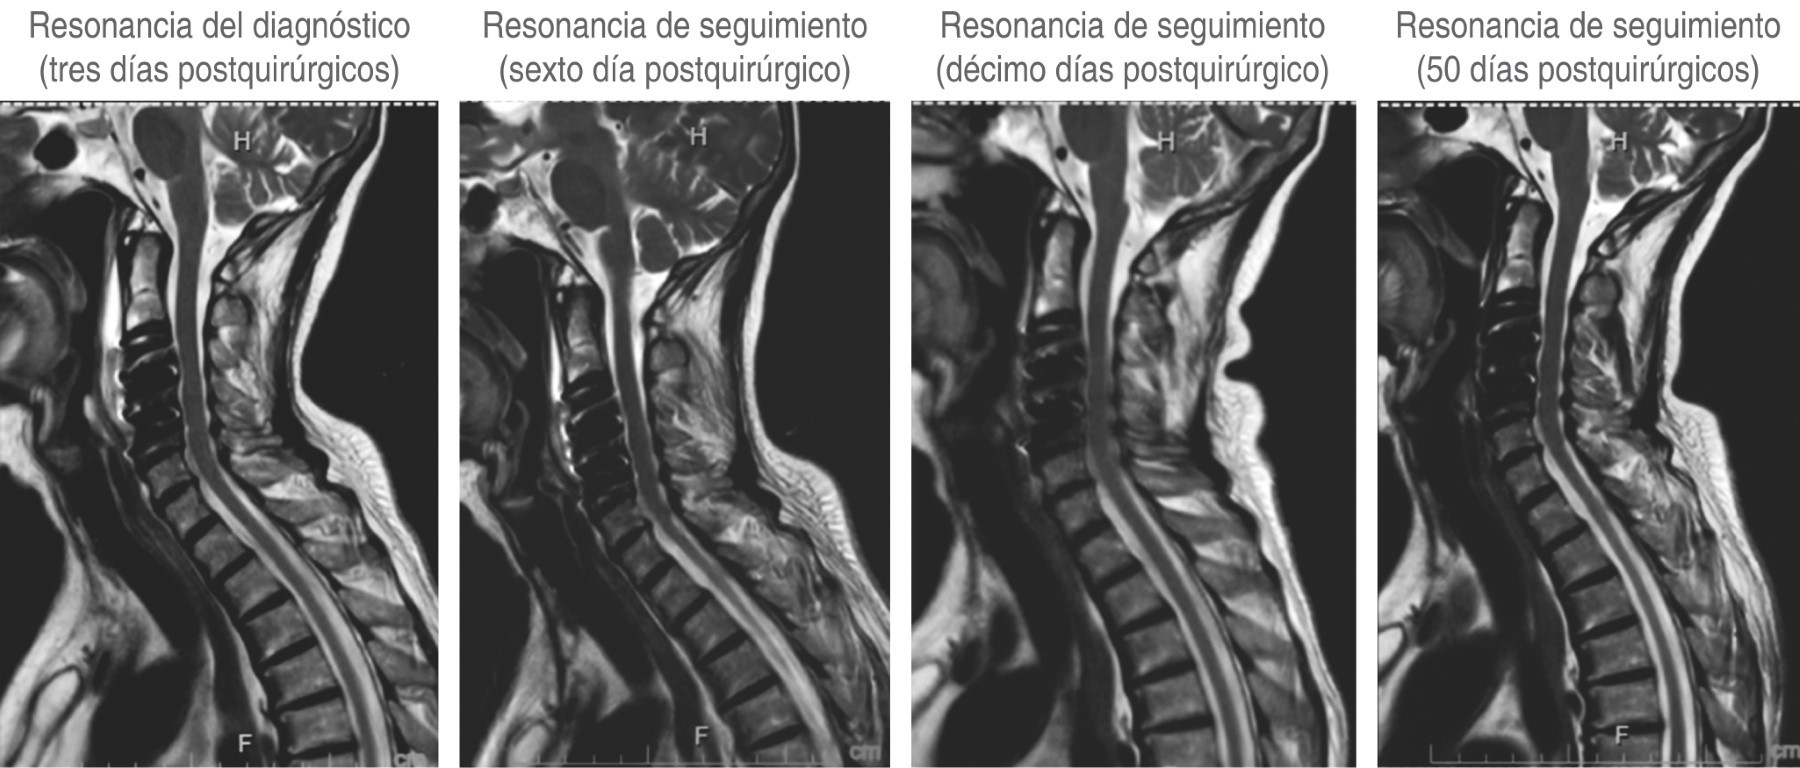

A tres pacientes se les realizó resonancia magnética de columna cervical simple (Figuras 3, 4 y 5), los días de realización variaron debido a que dos de ellos se encontraban en institución pública y la accesibilidad a la resonancia magnética no pudo ser inmediata. En los tres se presentó una hiperintensidad con forma de flecha, la cual se localizaba en el espacio prevertebral y que llegaba hasta C1-C2 (Figuras 3, 4 y 5). La hiperintensidad era isointensa respecto al líquido cefalorraquídeo que se observaba en el conducto raquídeo. En uno de los casos se pudo documentar un trayecto fistuloso, pero no fue constante en ninguno.

En los tres casos se obtuvo una segunda resonancia de seguimiento, la cual aproximadamente fue una semana después de la primera, y documentó la disminución notable del tamaño de la hiperintensidad prevertebral (Figuras 3, 4 y 5).

En sólo uno de los casos con fístula advertida hubo necesidad de reintervenir a la paciente retirando el sistema de osteosíntesis, sellando y suturando de nuevo el defecto dural y recolocando el material de osteosíntesis (Figura 3).

Como se puede observar en las imágenes previas, en la secuencia T2 en un corte sagital puede observarse una hiperintensidad en el espacio intervertebral que nos indica que en ese sitio se encuentra impregnado de líquido cefalorraquídeo, ya que la hiperintensidad es igual a la observada en el conducto raquídeo.

La segunda resonancia de seguimiento se realizó aproximadamente una semana después de la resonancia de diagnóstico y ésta nos permitió evaluar tanto con la atenuación en la intensidad, como en la disminución del tamaño, que no había fistula activa y que el paciente se encontraba en proceso de resolución de la fístula.

Como se puede observar en las imágenes previas, en la secuencia T2 en un corte sagital puede observarse una hiperintensidad en el espacio prevertebral que nos indica que en ese sitio se encuentra impregnado de líquido cefalorraquídeo, ya que la hiperintensidad es igual a la observada en el conducto raquídeo.

La segunda resonancia de seguimiento se realizó aproximadamente una semana después de la resonancia de diagnóstico, y ésta nos permitió evaluar tanto la disminución del volumen de la intensidad, como la atenuación de la hiperintensidad, que la fistula ya no se encontraba activa y que el paciente se encontraba en proceso de resolución de la complicación.

En el primer caso se observa que el líquido se encontraba hacia arriba y hacia abajo del sitio operado y el grosor de la hiperintensidad prevertebral era sumamente grande y que había discreta migración hacia el mediastino, lo que orilló a tomar la decisión de reintervenir a la paciente inmediatamente para cierre de fístula. Esto podría considerarse un signo de fístula de alto gasto, sin embargo, no se cuenta con suficiente evidencia como para sustentarlo, haría falta más evidencia para poderlo determinar.

El signo de la flecha puede ser un indicador muy fiable para el diagnóstico y seguimiento de las fístulas de LCR originadas en la discectomía de la columna cervical realizada vía anterior (Figuras 6 y 7). La misma se visualiza mejor en la secuencia T2 en el corte sagital de una resonancia magnética simple de columna cervical. Su identificación puede ayudarnos a tomar decisiones sobre esta pequeña gran complicación.